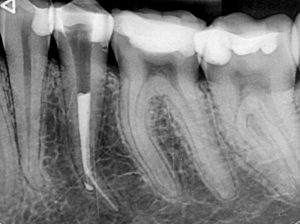

Случай на релечение на долен пети зъб, в който предишният колега беше фрактурирал канален инструмент и в опита си да довърши

лечението бе перфорирал и корена на нивото на извивката.

Освен перфорацията, извивката и счупения канален инструмент,

сложността на случая идваше и от факта, че коренът беше изключително тесен в областта на

извивката и имаше голяма опасност при

премахването на инструмента зъбът допълнително да се отслаби на

това място.

След изключително щадящо премахване на инструмента,

каналът бе обработен до невероятните 27 мм.

След което, заедно с перфорацията, беше запълнен с

биокерамичен сийлър